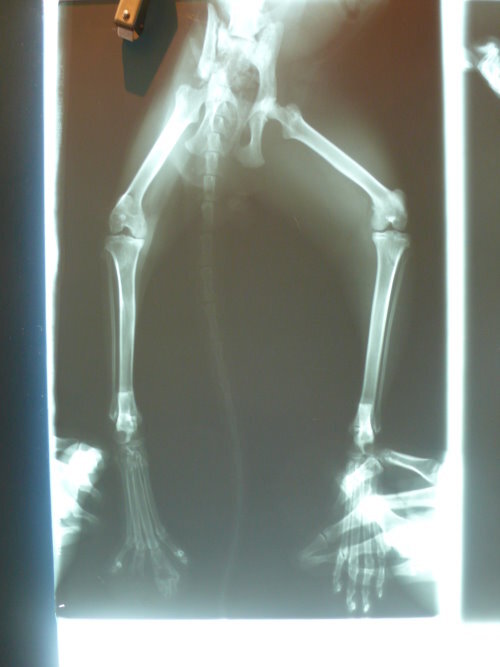

主題: 車禍骨折的虎斑貓-喬巴 申請者姓名: 林素蘭 花色: 申請日期: 2012-09-01 03:40:48 申請者部落格: 申請者臉書網址: 所在縣市/合作醫院: 台北市/長沁動物醫院 治療費用: 40000元 需求人數: 43人 已結案 (2012-12-08 18:49:02) 報名人員: 蘇小吉(已付款)、蘇小吉、angelcat(已付款)、Kelly(已付款)、曾美蓮(已付款)、Moon Wu(已付款)、May Chuang(已付款)、Andy Wang(已付款)、Patrick Liu(已付款)、小霸王叮噹(已付款)、趙君綺(已付款)、李婕瑜(已付款)、Chuck Lin(已付款)、李水晶(已付款)、meemee(已付款)、Grant Tsai(已付款)、何怡平(已付款)、曹博涵(已付款)、chiawei(已付款)、Wen-Chieh Juan(已付款)、meg(已付款)、味噌(已付款)、Chenyu Chang(已付款)、nicole chen(已付款)、何偉靖(已付款)、H.l. Lai(已付款)、yymeow(已付款)、yushi0304(已付款)、boodan(已付款)、Zoe Chen(已付款)、WUTI(已付款)、Wei(已付款)、Wei(已付款)、Wei(已付款)、Wei(已付款)、Wei(已付款)、Wei(已付款)、Wei(已付款)、Wei(已付款)、Wei(已付款)、Wei(已付款)、Rinee(已付款)、Yi-Sheng Lee(已付款)、林螢逸(已付款)、 候補人員: 小舟、小舟、 動物病情說明: 貓咪突然出現在餵食的區域,非常的怕人,吃東西總是很迅速,一吃完馬上跑走,無意見發現他經過的地方都會濕濕的,隔天特別觀察發現貓咪跛行且有開放性傷口,經捕捉就醫,小虎是腳踝骨折無法正常行走,拖行導致腳背感染潰爛見骨,第三~第四趾骨細菌感染導致骨融解,經醫師評估後決定截除已溶解之第三第四趾骨,並保留掌墊部分供日後行走承重之用,並架設兩段式外固定,提供腳踝骨頭癒合支撐之用並可兼顧每天換藥的需求,經一個月治療後已可行走並精神食欲皆佳,已帶回照顧。費用部分還請大家幫幫忙。